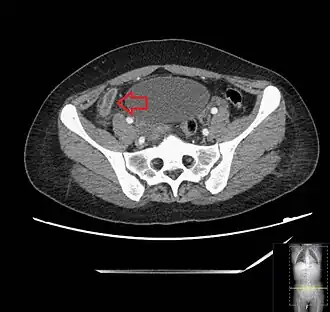

A CT scan demonstrating acute appendicitis (note the appendix has a diameter of 17.1 mm and there is surrounding fat stranding).

A fecalith marked by the arrow that has resulted in acute appendicitis.

Where it is readily available, computed tomography (CT) has become frequently used, especially in people whose diagnosis is not obvious on history and physical examination. Although some concerns about interpretation are identified, a 2019 Cochrane review found that the sensitivity and specificity of CT for the diagnosis of acute appendicitis in adults was high.[63] Concerns about radiation tend to limit use of CT in pregnant women and in children, especially with the increasingly widespread usage of MRI.[64][65]

The accurate diagnosis of appendicitis is multi-tiered, with the size of the appendix having the strongest positive predictive value, while indirect features can either increase or decrease sensitivity and specificity. A size of over 6 mm is both 95% sensitive and specific for appendicitis.[66]

However, because the appendix can be filled with fecal material, causing intraluminal distention, this criterion has shown limited utility in more recent meta-analyses.[67] This is as opposed to ultrasound, in which the wall of the appendix can be more easily distinguished from intraluminal feces. In such scenarios, ancillary features such as increased wall enhancement as compared to adjacent bowel and inflammation of the surrounding fat, or fat stranding, can be supportive of the diagnosis. However, their absence does not preclude it. In severe cases with perforation, an adjacent phlegmon or abscess can be seen. Dense fluid layering in the pelvis can also result, related to either pus or enteric spillage. When patients are thin or younger, the relative absence of fat can make the appendix and surrounding fat stranding difficult to see.[67]